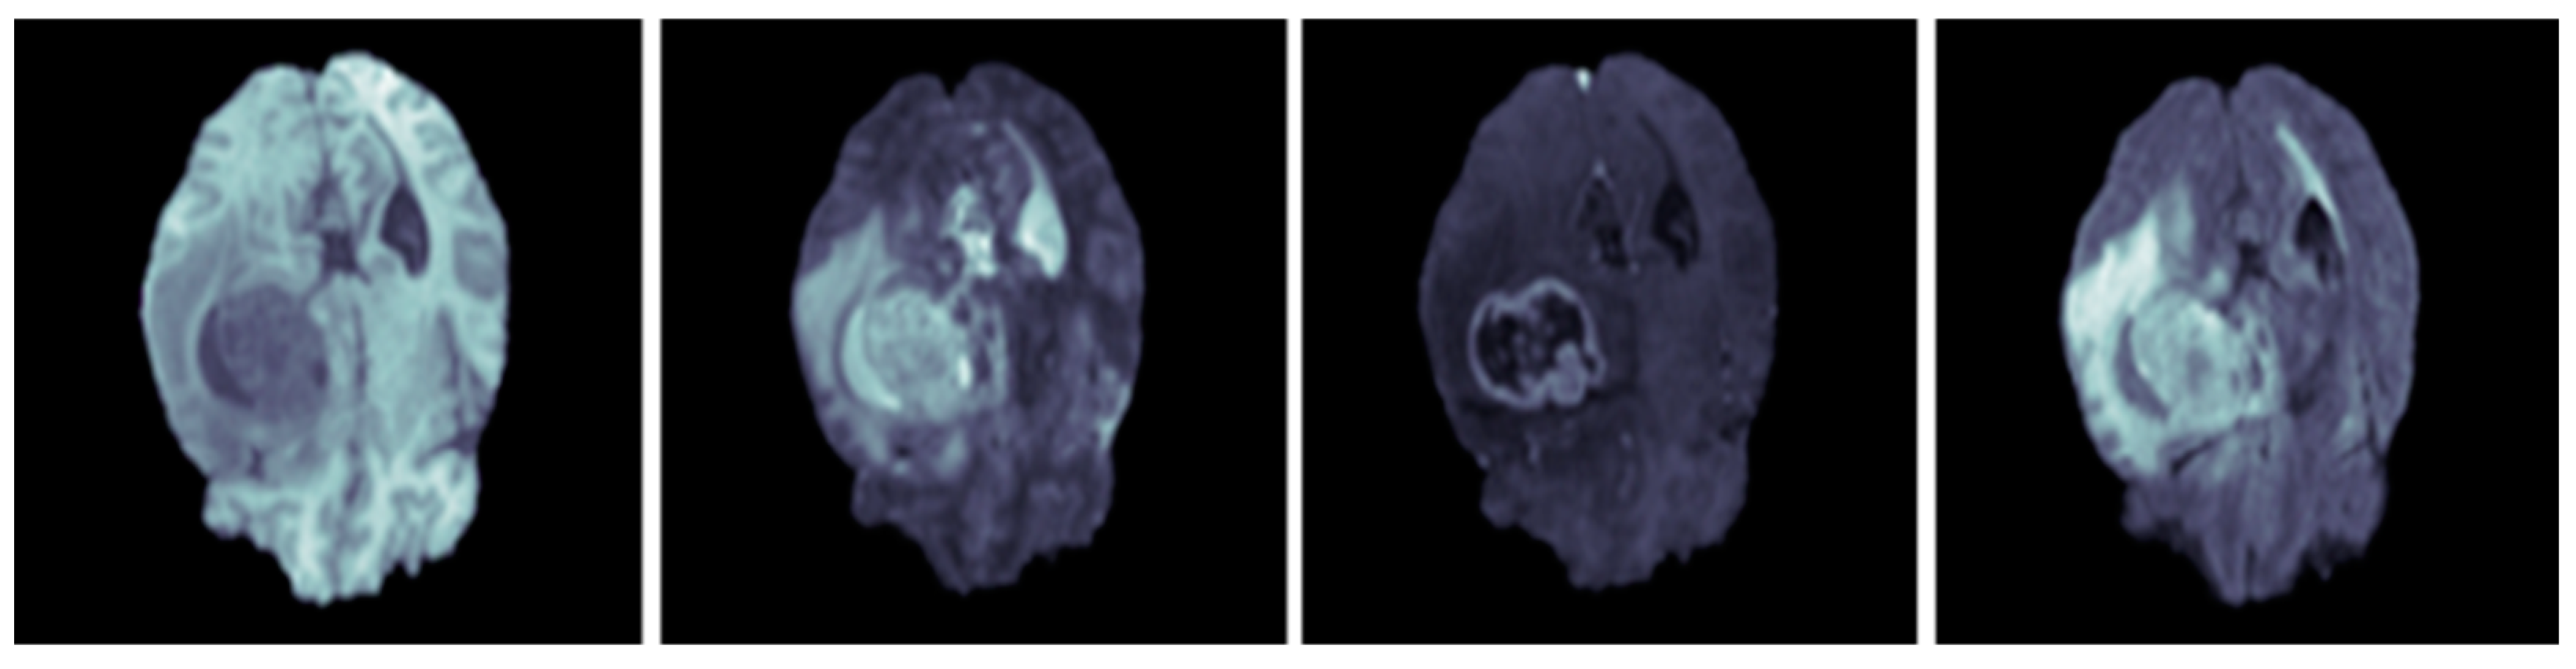

Modalities of the BraTS 2020 database are equipped with manual segmentation of lesions and consist of 125 subject data without the manual ground truth which can be used for comparison. Example MRI scans of the BraTS 2020 database are included in Figure 3.

Figure 3.

Example MRI brain scans of BraTS 2020 database [35].